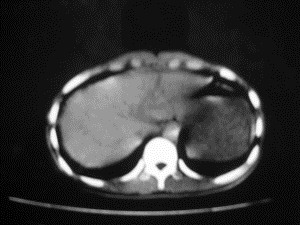

患者女,20岁,被车撞伤3小时,pe:全腹肌紧张,压痛反跳痛,以右上腹为著,肠鸣音减弱。有手术结果。![]() ![]() ![]() ![]() ![]() ![]() ![]() ![]() ![]() ![]() ![]() ![]() ![]() ![]() ![]() ![]() ![]() ![]() ![]() ![]() ![]() jiajie发言: ![]() 考虑空腔脏器穿孔。 dyqct发言:考虑:1、肝左叶外侧段断裂伤伴少量腹血。2、空腔脏器穿孔。 fangzheng发言:仅见腹腔内游离气体,提示空腔脏器穿孔。 guoke发言:胃内密度增高,肠腔内充满气体,考虑肠腔破裂出血 mmg94发言:胃后壁见一增厚软组织密度影,肝左叶前见游离气体影,左腹腔内局部肠管壁、系膜增厚。并见类圆形软组织。以上征象提示消化道管腔破裂,小肠、肠系膜挫裂伤,腹腔血肿形成。 拾荒者发言:肝实质密度不均匀,胃内见不均匀高密度影。考虑:肝挫裂伤,胃内应激性溃疡出血。 守望可可西里发言: 以下是引用jiajie在2006-6-20 15:49:00的发言:[br] [br][br]考虑空腔脏器穿孔。jiajie老师,我鼓起了很大的勇气才决定给您唱个反调儿,如果我错了,请您一定给我指出来,谢谢您了。我反复看了解剖图谱,觉得您所说的“考虑空腔脏器穿孔”上图所用箭头标明的不是游离气体。请您看以下几幅图片: ![]() ![]() ![]() ![]() ![]() ![]() ![]() ![]() 再请您看向医生老师发表的解剖图谱3幅 ![]() ![]() ![]() 这以下几幅图,我认为是肝包膜下积血。不过,说实在话,我没有发现有明显的肝挫裂伤。不对的地方请您一定指出来,再次感谢您了,jiajie 老师! ![]() ![]() ![]() ![]() 这下面几幅图片,我认为有明显的左中上腹部小肠损伤。 ![]() ![]() ![]() ![]() ![]() ![]() ![]() ![]() jiajie 老师,估计我说的是错误的,但我实在闹不明白,请您一定不要笑话我,并指出我的错误,以便于我减少工作中的失误。再次感谢您了,jiajie 老师! 至于胃内的不均匀高密度,我认为拾荒者战友说的有道理,胃内应激性溃疡出血和胃内容物混合所致。 手术结果:左肝叶(iv段)前缘长约8cm挫裂伤口,舌叶根部下< |